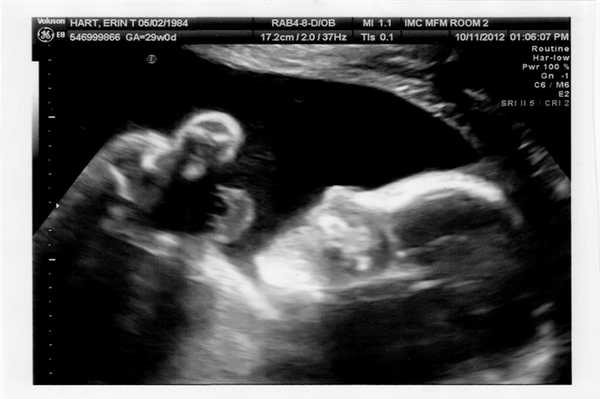

Фото УЗИ ребенка на разных сроках беременности

Если беременность желанная, будущие родители внимательно относятся к пренатальной диагностике плода. Чтобы убедится, что ребенок развивается нормально, в течение 9 месяцев гинеколог несколько раз направляет женщину на ультразвуковое исследование. Фото УЗИ может многое рассказать врачу и будущим родителям о малыше. Кроме того, снимок станет трогательным напоминанием для семейного архива.

Чтобы сделать фото УЗИ малыша на разных сроках, беременной женщине необходимо записаться на ультразвуковой скрининг в медицинском центре «Диана».

Фото УЗИ ребенка на 27-28 неделе беременности

На финальной стадии находится развитие всех частей организма малыша. В случае преждевременных родов он уже готов к самостоятельному выживанию. Малыш может открывать глаза, ощущает вкус, слышит все звуки, способен различать запахи. Половые органы полностью сформированы, что позволяет по фото УЗИ точно удостовериться, кого ожидает женщина.